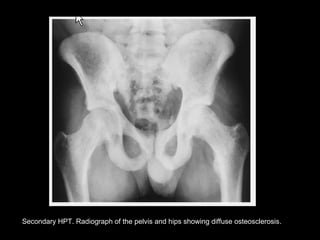

Secondary HPT. Radiograph of the pelvis and hips showing diffuse osteosclerosis.

Secondary HPT. Radiographof the pelvis and hips showing diffuse osteosclerosis.

Radiologic findings ofRadiologic findings of

HYPERPARATHYROIDISMHYPERPARATHYROIDISM

SecondarySecondary

• Bony sclerosis; focal

or generalized.

• Rugger-jersey

appearance of

spine.

• Soft tissue and

vascular

calcification.